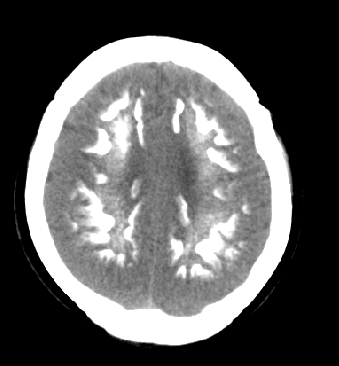

女性 38岁 病人脚弓反张 8岁以后不能行走 今年查pth11.9ng/ml(正常28ng/ml)

这么弥漫的钙化还第一次见。

考虑甲状旁腺功能减退症,该病是因甲状旁腺激素分泌减少或功能障碍所引起的少见病。其特点是低血钙,高血磷,且血pth极低。因低钙常可引起神经精神激惹症状,包括手指,趾,口角麻木,严重时可出现肌肉痉挛,喉哮鸣和惊厥,甚至癫痫样发作,有的可出现抑郁症及精神失常。长期的高磷血症可引起脑内结构对称性多发性钙化,特别是小脑和基底节的钙化可致锥体外系症状,而钙化的ct表现为类似于脑出血的密度增高影。

鉴别诊断:fahr 病,又称特发性家族性脑血管亚铁钙沉着症,是一种少见病,男女发病无显著差异,多为散发。临床表现为阵发性意识不清,首发症状开始于14~51 岁不等,以后呈阵发性发作,表现为突然神志丧失、跌倒、四肢抽搐约,发作后常表现为意识淡漠,性格改变,血清钙在正常范围。ct表现尾状核头呈倒“八”字形或片状钙化,在大脑半卵圆中心皮、髓质交界处多为点、小片状钙化,丘脑多呈对称小点、小条状钙化,小脑齿状核呈括弧形或不对称性小片状钙化。

原发性甲状旁腺功能减退症和fahr病都有神志上的改变等症状,且头颅ct检查均可见颅内出现钙化。但fahr病无pth低下,ct表现钙化影在大脑半卵圆中心皮髓质交界处、丘脑、小脑齿状核等处。 而甲状旁腺功能减退症pth极低,ct虽可见钙化影,但部位在小脑和基底节等处。